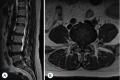

Surgical treatment of the degenerative disc disease has evolved from traditional open spine surgery to minimally invasive spine surgery including endoscopic spine surgery. Constant improvement in the imaging modality especially with introduction of the magnetic resonance imaging, it is possible to identify culprit degenerated disc segment and again with the discography it is possible to diagnose the pain generator and pathological degenerated disc very precisely and its treatment with minimally invasive approach. With improvements in the optics, high resolution camera, light source, high speed burr, irrigation pump etc, minimally invasive spine surgeries can be performed with various endoscopic techniques for lumbar, cervical and thoracic regions. Advantages of endoscopic spine surgeries are less tissue dissection and muscle trauma, reduced blood loss, less damage to the epidural blood supply and consequent epidural fibrosis and scarring, reduced hospital stay, early functional recovery and improvement in the quality of life & better cosmesis. With precise indication, proper diagnosis and good training, the endoscopic spine surgery can give equally good result as open spine surgery. Initially, endoscopic technique was restricted to the lumbar region but now it also can be used for cervical and thoracic disc herniations. Previously endoscopy was used for disc herniations which were contained without migration but now days it is used for highly up and down migrated disc herniations as well. Use of endoscopic technique in lumbar region was restricted to disc herniations but gradually it is also used for spinal canal stenosis and endoscopic assisted fusion surgeries. Endoscopic spine surgery can play important role in the treatment of adolescent disc herniations especially for the persons who engage in the competitive sports and the athletes where less tissue trauma, cosmesis and early functional recovery is desirable. From simple chemonucleolysis to current day endoscopic procedures the history of minimally invasive spine surgery is interesting. Appropriate indications, clear imaging prior to surgery and preplanning are keys to successful outcome. In this article basic procedures of percutaneous endoscopic lumbar discectomy through transforaminal and interlaminar routes, percutaneous endoscopic cervical discectomy, percutaneous endoscopic posterior cervical foraminotomy and percutaneous endoscopic thoracic discectomy are discussed.